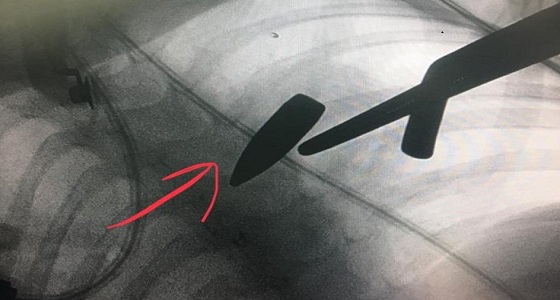

بالصور.. إصابة طفل برصاصة في الصدر بوادي الدواسر في حفل زواج

منذ 7 سنة

2

4902

نور.. 7 أيام والرصاصة لا تزال في قلبها!

منذ 8 سنة

2

6760